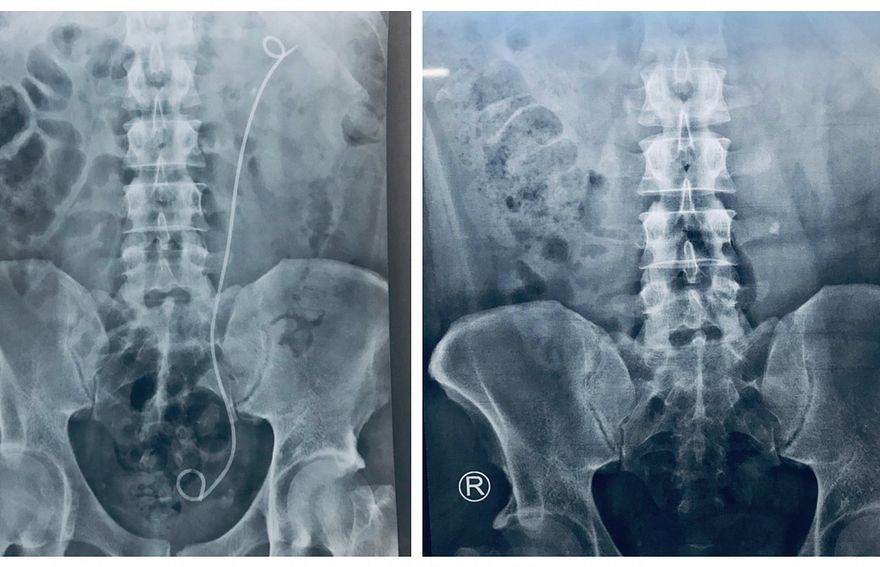

އަދީބުގެ އަނބިކަނބަލުން މަރިޔަމް ނަޝްވާ ވިދާޅުވީ އަދީބުގެ އޮޕަރޭޝަނަށް ފަހު އެތެރެހަށީގެ ޔޫރެޓްރާއަށް ސްޓެންޓެއް ލައްވާފައިވާ ކަމަށެވެ. އަދި އޮޕަރޭޝަނަށް ފަހު، އިންފެކްޓުވެ ހުން އައުމާ ގުޅިގެން އެންޓިބަޔޮޓިކްސް ދެމުން އަންނަ ކަމަށް ވެސް ނަޝްވާ ވިދާޅުވި އެވެ.

ނަޝްވާ ވިދާޅުވި ގޮތުގައި، އަދީބުގެ ހަށިގަނޑުގައި އުފެދުނު ހިލަ ނެގުމަށް ކުރި އޮޕަރޭޝަންގެ ސަބަބުން ހިލައިގެ އެއްބައި ހަށިގަނޑުން ބޭރުވިޔަސް، އަދިވެސް އެއް ބައި ހަށިގަނޑު ތެރެއިން ފެނެެެއެވެ.

"ޑޮކްޓަރު ލަފާ ދެއްވާފައި ވަނީ އެ ބައި ވެސް އަމިއްލައަށް ފްލަޝްވާނެ ކަމަށް. އެކަމަކު އެއީ ސްޓްރެސް ފްރީ ފެމިލީ ކެއާ ލިބޭ ގޮތަށް ގޭބަންދުގައި ބެހެއްޓީމައޭ ޑޮކްޓަރު އެންގެވީ،" ނަޝްވާ ވިދާޅުވި އެވެ.